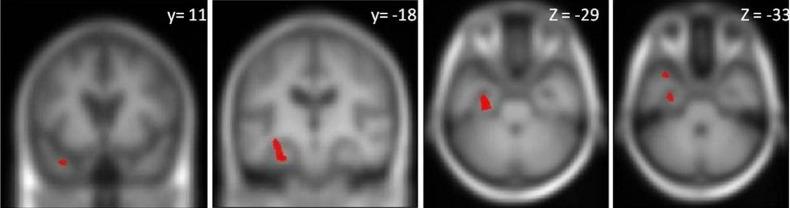

Relative to the healthy control group, the bvFTD and svPPA subgroups showed significant (p<0.05) deficits of flavour identification and all three FTLD subgroups showed deficits of odour identification. Flavour identification performance did not differ significantly between the FTLD syndromic subgroups. Flavour identification performance in the combined FTLD cohort was significantly (p<0.05 after multiple comparisons correction) associated with grey matter volume in the left entorhinal cortex, hippocampus, parahippocampal gyrus and temporal pole.

与健康对照组相比,bvFTD 和 svPPA 亚组表现出明显的(p<0.05)味觉识别缺陷,所有三个 FTLD 亚组均表现出嗅觉识别缺陷。FTLD 综合征亚组之间的味觉识别性能没有显著差异。在联合 FTLD 队列中,味觉识别性能与左侧内嗅皮质、海马体、海马旁回和颞极的灰质体积显著相关(经多次比较校正后 p<0.05)。